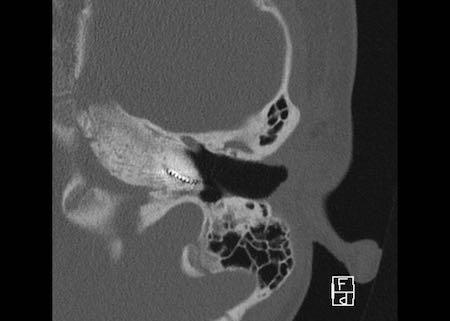

Ca lâm sàng 2

Các hình ảnh này cho thấy một điện cực cấy ghép bị lạc chỗ.

Điện cực ốc tai được đưa vào phía dưới vòng đáy của ốc tai và kết thúc ở vùng hạch gối (geniculate ganglion).